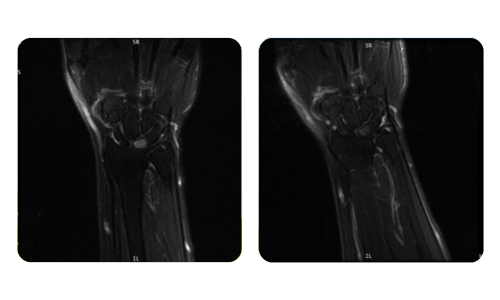

I progressi dei nostri pazienti, misurati prima e dopo la terapia iperbarica, riflettono l'efficacia e l'impatto positivo del trattamento. Scopri i risultati documentati della terapia iperbarica presso la clinica Hyperbarium Oradea, basati su valutazioni cliniche e dati oggettivi che evidenziano miglioramenti significativi in diverse condizioni.